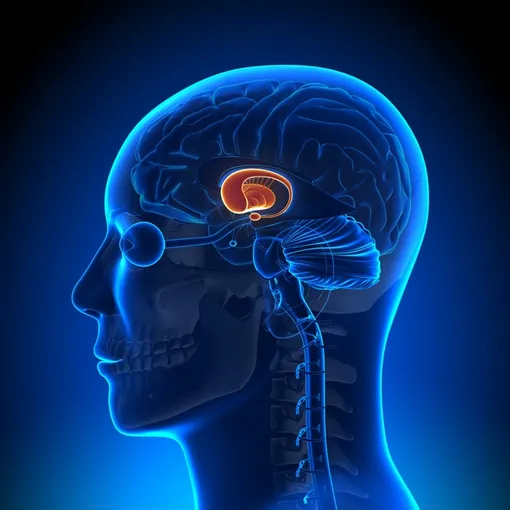

Новая генная терапия использует безвредный вирус для доставки в пораженные участки мозга инструкций по производству микроРНК. Эта молекула блокирует работу дефектного гена, останавливая выработку токсичного белка. После однократного введения клетки продолжают производить терапевтическую микроРНК постоянно. Процедура требует сложной нейрохирургической операции с применением МРТ-навигации для точного введения препарата в стриатум — область мозга, наиболее пораженную при болезни Хантингтона.